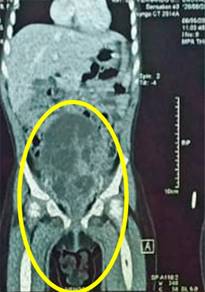

La paciente se hospitaliza para realizar tomografía; el estudio confirmó la presencia de una masa intravesical de 4 × 3 cm de diámetro y 5 × 3 cm de longitud, con lesiones hiperdensas con centros hipodensos (Figura 3); además se observaron ganglios linfáticos inguinales bilaterales de aspecto reactivo e hidronefrosis bilateral grado 2. Pero sin evidenciar metástasis a distancia (Figura 4).

Figura 3: Tomografía simple de abdomen, corte coronal. Se observa masa a nivel vesical, multilobulada con contorno hiperdenso y centro hipodenso múltiples, de aproximadamente 4 × 5 cm.

Figura 4: Tomografía simple de abdomen con corte coronal con masa a nivel vesical, pero sin metástasis.